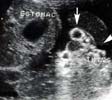

- Hernie développée en regard de l’ombilic, à paroi fine :

* Mesures de l’omphalocèle,

* Diamètre du collet ( > à 3 cm).

- Contenu : intestin grêle, foie, vésicule, estomac, ascite...,

- Implantation du cordon sur l’omphalocèle,